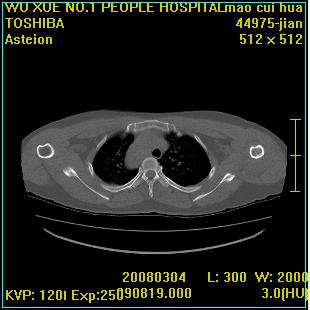

标题: CT12025:男,50岁,左肩活动受限半年。 [打印本页]

标题: CT12025:男,50岁,左肩活动受限半年。

肩关节骨质破坏呈小囊状,其周软组织轻度肿胀,余未见异常。

考虑:肩袖损伤。建议mri。

左侧肱骨头密度不均匀,高低混杂,周围软组织略肿胀,考虑结核性病变。

考虑左侧肱骨慢性骨髓炎。

左侧肱骨头密度不均匀,高低混杂,髓腔密度稍高,周围软组织略肿胀,肌间隙模糊,考虑慢性骨髓炎可能。密切结合临床!